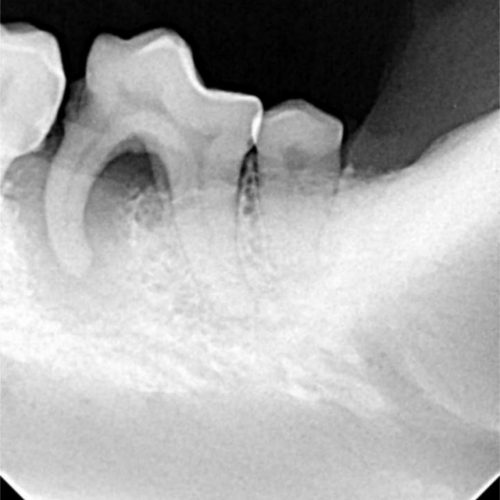

Odontología

La salud dental es vital para el bienestar general de tu mascota. Realizamos limpiezas dentales con ultrasonidos, tratamientos odontológicos específicos y cirugías orales cuando es necesario. Una boca sana evita infecciones, dolor y mejora su calidad de vida.